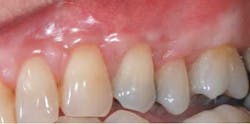

Postop: Nine-month reevaluation